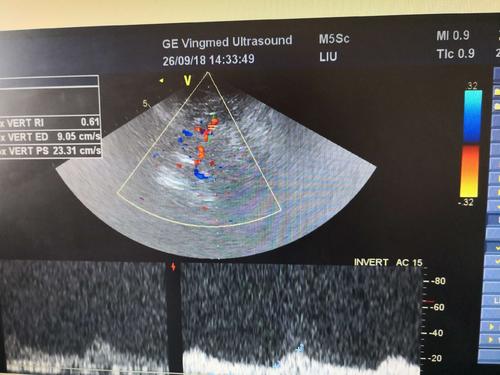

經(jīng)顱彩色編碼雙功能超聲,區(qū)別于經(jīng)顱多普勒超聲,它的英文簡稱是TCCD,后者是TCD。TCCD成像模式是什么樣的,tcd廠家澳思泰今天來分析這一問題。

TCCD成像模式

(1)依據(jù)多普勒頻移值編碼成像即f-TCCD:

依賴運動紅細(xì)胞所產(chǎn)生的多普勒頻移值進(jìn)行計算機(jī)編碼,可以顯示血流方向和測算血流速度,需要校正多普勒取樣角度,角度及篩查深度依賴性較大,較易產(chǎn)生運動偽像。

(2)依據(jù)運動紅細(xì)胞所產(chǎn)生的總能量進(jìn)行編碼成像即p-TCCD:

只與運動紅細(xì)胞所產(chǎn)生的總能量有關(guān),無需校正多普勒取樣角度,對于受取樣角度影響較大血管病變,諸如大腦后動脈(PCA),大腦中動脈(MCA)M2段,大腦前動脈(ACA)A1段有一定的幫助作用,信噪比更高,不易產(chǎn)生混疊效應(yīng)。p-TCCD相對f-TCCD而言,缺點是不能顯示血流方向,對顯示狹窄處高速血流敏感性較低。